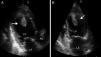

Case reportA 27-year-old primigravida woman presented in the emergency room seven days after an uncomplicated spontaneous vaginal delivery. She complained of recurrent temporary speech disturbance and visual impairment twice within six hours. The pregnancy was uneventful and her medical history was insignificant. On physical examination, blood pressure was 110/65 mmHg with a regular heart rate of 105 bpm. Bilateral grade 1–2 pitting pedal edema was present. Carotid auscultation and fundoscopic evaluation were normal. Chest auscultation showed bibasal crackling rales less than one-half way up the posterior lung fields and an apical III/VI systolic murmur with S3 gallop. The electrocardiogram showed normal sinus rhythm. The chest X-ray on admission showed cardiomegaly and pulmonary edema with bilateral pleural effusion. Urgent neurologic investigation with computed brain tomography revealed no evidence of ischemia (Figure 1). The patient was diagnosed with transient ischemic attack. Laboratory tests, including coagulation studies with platelets, D-dimers, prothrombin time and activated partial thromboplastin time, were within the normal range except for BNP, which was elevated (1300 pg/ml; normal <100 pg/ml) and C-reactive protein (0.30 mg/dl; normal <0.5). The thyroid hormone profile was normal. Transthoracic echocardiography (TTE) showed global left ventricular hypokinesia, left ventricular end-diastolic dimension of 65 mm with an ejection fraction of 22% (by Simpson's method) and moderate mitral regurgitation. A large mobile mural thrombus was observed in the left ventricular apex (Figure 2A and B). Screening for thrombophilia including antithrombin III, protein C and S, plasminogen, fibrinogen and homocysteine levels was normal and antiphospholipid antibodies, β2-glycoprotein I and anticardiolipin antibodies IgG and IgM were negative. Factor V Leiden, prothrombin 20210A polymorphism and MTHFR mutations were not found. The patient was immediately started on intravenous anticoagulation with low molecular weight heparin as well as angiotensin-converting enzyme inhibitors, diuretics and digoxin. A beta blocker (carvedilol) was added after signs and symptoms of congestive heart failure improved. By one month of follow up she had responded well to medical therapy and was asymptomatic; repeat TTE showed no evidence of thrombi in the left ventricle and ejection fraction had improved to 38%.